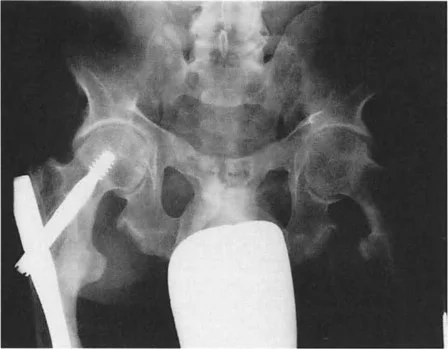

3. تحميل المفصل غير الطبيعي ومتجه رد فعل الأرض (GRV)

متجه رد فعل الأرض (Ground Reaction Vector - GRV) هو القوة المحصلة التي تؤثر بها الأرض على القدم عند نقل وزن الجسم أثناء الوقوف. يتم تحديدها بواسطة قانون نيوتن الثالث. في طرف سفلي متوافق تمامًا، يمر متجه رد فعل الأرض مباشرة عبر مركز مفاصل الورك والركبة والكاحل في كل من المستويين الأمامي والسهمي. وهذا يضمن توزيعًا متساويًا وفسيولوجيًا لقوى الضغط عبر الغضروف المفصلي.

تزيح تشوهات العظام متجه رد فعل الأرض بعيدًا عن مركز المفصل، مما يخلق عزم دوران مرضيًا.

أمراض المستوى الأمامي (التقوس/الفحج - Varus/Valgus):

إذا كان المريض يعاني من تشوه تقوس (Varus) في عظم الساق أو الفخذ، فإن متجه رد فعل الأرض يتحرك نحو الداخل (إنسيًا). كلما مر متجه رد فعل الأرض أكثر إنسيًا بالنسبة لمركز الركبة، زاد عزم دوران التقريب. وهذا يزيد بشكل كبير من قوى الضغط على الجزء الإنسي من سطح عظم الساق القريب (medial tibial plateau).

بينما يحمل الوقوف على ساق واحدة طبيعيًا الجزء الإنسي بحوالي 75%، فإن تشوه التقوس الشديد (الذي يسبب انحرافًا كبيرًا في المحور الميكانيكي، أو MAD) يمكن أن ينقل 100% من الحمل إلى الجزء الإنسي. على مدى فترات طويلة، يؤدي هذا التحميل الميكانيكي الموضعي المفرط إلى تدهور سريع وتدريجي للغضروف المفصلي، وتصلب تحت الغضروف، وتكون نتوءات عظمية، وفي النهاية إلى التهاب مفصل الركبة في مراحله المتأخرة.